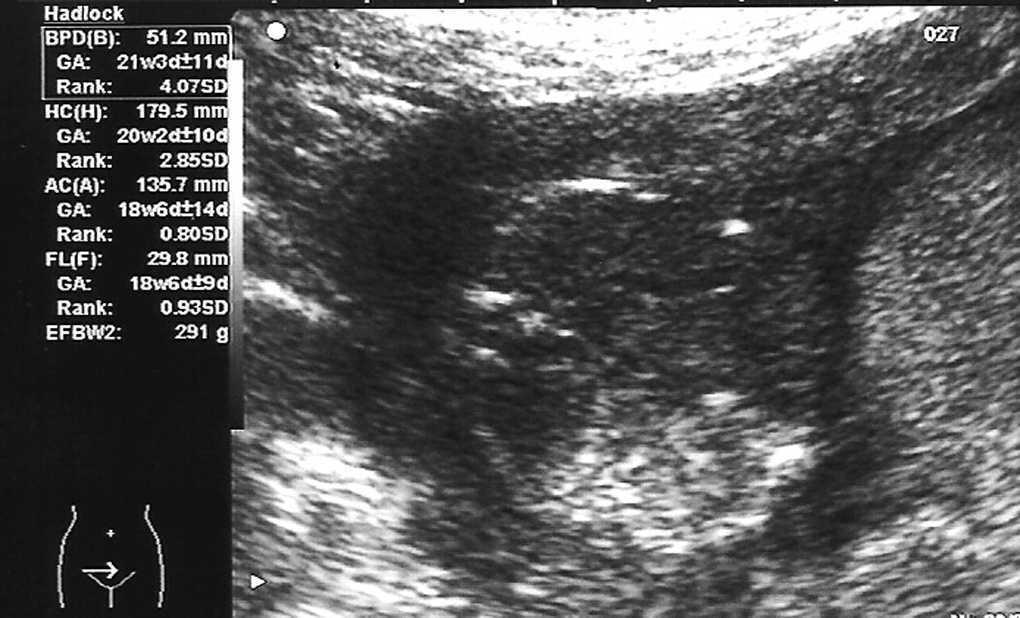

Octavigesta de 41 años, con embarazo no controlado, a quien en la semana 20 se objetiva un feto con somatometría y peso correspondientes a 17-18 semanas; la paciente no acudió a posteriores controles y rechazó la posibilidad de técnica invasiva para estudio de cariotipo. En semana 25 + 5 se remite a la unidad de medicina maternofetal con el diagnóstico de retraso de crecimiento intrauterino (RCIU) precoz y severo. En el estudio realizado se objetiva un feto en cefálica con diámetro biparietal (DBP) de 51,2 mm, circunferencia craneal (HC) de 179,5 mm, circunferencia abdominal (AC) de 135,7 mm y longitud femoral (LF) de 29,8 mm, con peso fetal estimado (PFE) de 291 g, muy por debajo de los percentiles (menor de percentil 3) para 25-26 semanas de embarazo (fig. 1). Presentaba una placentomegalia importante y un estudio Doppler con una onda de velocidad flujo (OVF) en arteria umbilical patológica con ausencia de diástole y flujo reverso (fig. 2). Inicio de distribución de flujo en arteria cerebral media y conservaba flujos venosos. Oligoamnios prácticamente total. Con el diagnóstico de RCIU severo precoz con signos de insuficiencia placentaria, se explicó la situación a la paciente y se realizó estudio para cariotipo con QF-PCR, que estaba dentro de la normalidad. En posterior control ecográfico, no se evidenció la presencia de latido cardíaco fetal, y se confirmó el óbito del feto. En ese control, la paciente refería inicio de lesiones cutáneas en miembros inferiores intensamente pruriginosas. Tras administrar dinoprostona local se produjo la expulsión de un feto de 301 g y posterior legrado sin incidencias. En los días posteriores, el cuadro cutáneo progresó de forma acelerada desde los miembros inferiores a abdomen, miembros superiores, cuello, cabeza, boca, manos y pies; únicamente respetaba la cara (figs. 3-5). Se realizó biopsia de dichas lesiones que informó de la existencia de depósitos lineales de la fracción del complemento C3 y de IgG en la membrana basal de la piel afectada y en zonas perilesionales, compatible con un cuadro de HG.

Figura 1.Retraso del crecimiento fetal severo y precoz.

Figura 2.Onda de velocidad de flujo umbilical patológica con ausencia de diástole y flujo reverso.